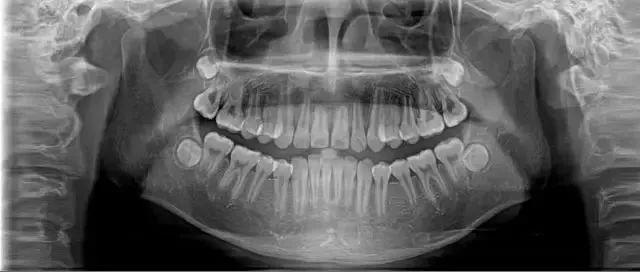

日前, 25歲的李女士因為牙齒松動、牙齦出血前來鄭州大學第一附屬醫(yī)院河南省口腔醫(yī)院就診。

醫(yī)生經(jīng)過系統(tǒng)檢查后,確定這位年輕人出現(xiàn)全口多處牙齒的松動,診斷為侵襲性牙周炎。

經(jīng)過口腔醫(yī)院診斷,她患上了嚴重的牙周炎,醫(yī)生先后為其拔除了11顆牙齒,并種植了10顆牙齒。

28歲的小孟因刷牙時突然一顆門牙脫落,當她到醫(yī)院就診時,醫(yī)生告訴她上排牙已全部不能保留。

小孟的牙齒已經(jīng)出現(xiàn)了不同程度的松動,而導致她松動至功能喪失的是嚴重的牙周炎。終只能將其牙拔去后,花費十五六萬元選擇種植牙。